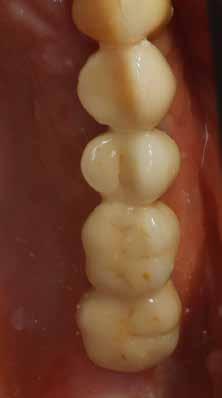

Hathetes gyógyulás után a lágyszövetek kiválóan gyógyultak, és minden implantátum megfelelően osszeointegrálódott, amelyet a radiológiai vizsgálat is megerősítetett (9. és 10. ábra).

Nyitott kanalas lenyomatvételi fejeket csatlakoztattunk az implantátumokhoz, és elasztomer lenyomat-anyagot fecskendeztünk köréjük és a lenyomatkanálba, hogy egyfázisú lenyomatot vegyünk. A minta laboratóriumi elkészítését követően a kimart vázra kerámia leplezés került, amelyet megfelelő festéssel tettek még természetesebbé. Ezt követően a pótlást közvetlenül az implantátumokhoz csatlakoztattuk, majd ellenőriztük a kontaktpontot és az okklúziót. Minden csavart 35 Ncm-es nyomatékra húztunk, majd a csavarnyílásokat teflonszalaggal és fényre kötő kompozittal zártuk (11. ábra).

A végső röntgenfelvételen láthatjuk az osszeointegrálódott implantátumokat, valamint a stabil kresztális gerincet az azonnal behelyezett, a rövid és a ferde, a tuberben elhorgonyzott implantátum körül (12. ábra).

A páciens teljesen elégedett volt az esztétikai és a funkcionális eredménnyel is, továbbá lenyűgözte a kezelés rövidsége, valamint a minimálisan invazív megoldása.